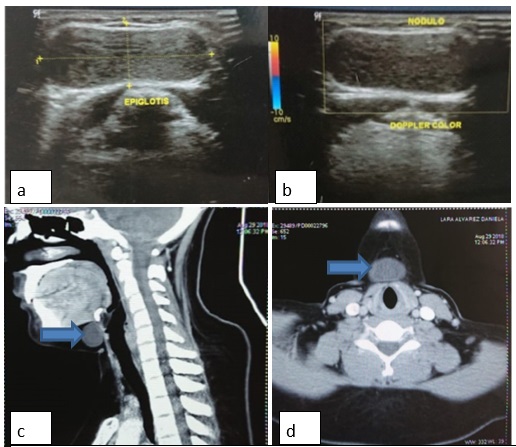

Femenino de 16 años de edad, sin antecedentes médicos de importancia, refiere aumento de volumen en la línea media del cuello a los 6 años de edad, que sigue los movimientos de la deglución sin causar otra sintomatología. En os últimos 6 meses presenta aumento progresivo en el volumen, negando antecedentes de infección de la tumoración. Refiere sensación de ahogo en posición decúbito dorsal. A la exploración física se encontró una masa en la línea media que sigue los movimientos de la deglución, con diámetro de aproximadamente 5x5 cm, fluctuante, no indurada, bordes lisos y regulares, indicativo de un quiste tirogloso (figura 1). En el ultrasonido de cuello se observó la glándula tiroides de características dentro de lo normal y una imagen de aspecto nodular en cuello que mide 34 x 12 x 22 mm, homogénea que no muestra vascularidad al doppler, por lo que se sugiere la realización de tomografía computarizada (TC) donde se identifica la presencia de una tumoración quística en la cara anterior del cuello, sobre la línea media a nivel infrahiodeo de 34 x 20 x 22 mm que sugiere probable quiste tirogloso (figura 2).

En el caso anteriormente mencionado al realizarse un ultrasonido este reportó una tumoración de características homogéneas, sin calcificaciones ni vascularización, lo cual no fue concluyente por lo tanto se solicitó una TC contrastada; las características homogéneas de la tumoración y la ausencia de calcificaciones contribuyeron al diagnóstico presuntivo de un quiste tirogloso más que un teratoma.

Figura 1. a y b: observe masa en línea media el cuello en región infrahiodea con bordes regulares.

Figura 2 a y b: Ultrasonido de cuello: observe imagen hipoecoica con cápsula no vascularizada al doppler. C y d: Tomografía de cuello en la cual se observa imagen isodensa a tejidos blandos localizada en región infrahiodea en la línea media (flechas azules)